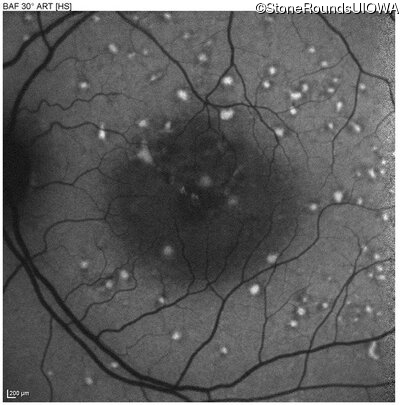

Pattern Dystrophy (IIC)

Age at visit: 49 years

This 49 year old man was first told he had a fundus abnormality on a routine eye exam at age 34. Ten years later he noticed some distortion just superior to fixation.

Pattern Dystrophy PRPH2 Gln239Stop CAG>TAG   AD